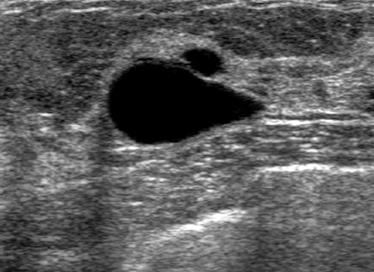

The target dataset was developed from 35 breast ultrasound scans that were segmented by an image-processing expert with extensive experience in breast lesion segmentation (the second author). The images, collected from the Web, are of different dimensions, ranging from to pixels (Figure 3, images resized for sake of illustration). These are the same images used to introduce EFIS originally [1].

Ultrasound images are generally difficult to segment, primarily due to the presence of speckle noise and low level of local contrast. It should be noted that the segmentation of ultrasound actually does require a complete processing chain, (including proper preprocessing and post-processing steps). However, the purpose of using these images was solely to demonstrate that the accuracy of the segmentation can be increased with the application of SC-EFIS.